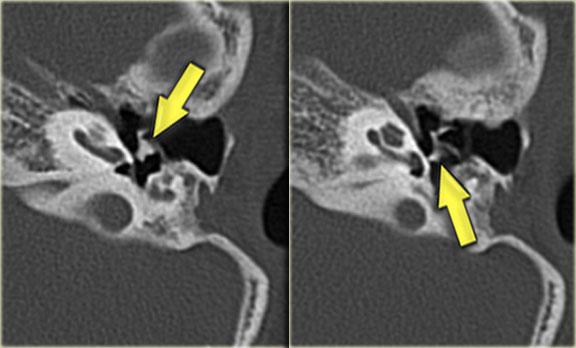

Hình ảnh bên trái của một nam bệnh nhân bị chấn thương đầu hai tháng trước.

Bệnh nhân than phiền về ù tai từng cơn.

Có đường gãy dọc (mũi tên vàng) đi qua xương chũm về phía vùng hạch gối.

Có trật xương đe với trật khớp búa-đe và khớp đe-bàn đạp (mũi tên xanh).

Không có tổn thương tai trong.

Tai trái để so sánh.

Hình ảnh bên trái của một nam bệnh nhân 54 tuổi, nhiều năm sau chấn thương đầu, kèm theo mất thính lực bên trái.

Có đường gãy ngang qua tiền đình và ống thần kinh mặt (mũi tên).

Ống bán khuyên ngoài bị lấp đầy một phần bởi chất đặc, phù hợp với viêm mê đạo cốt hóa.